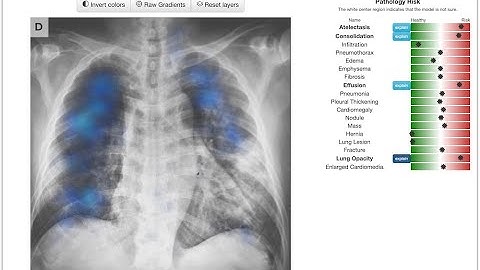

ScanSense—your AI radiology report assistant